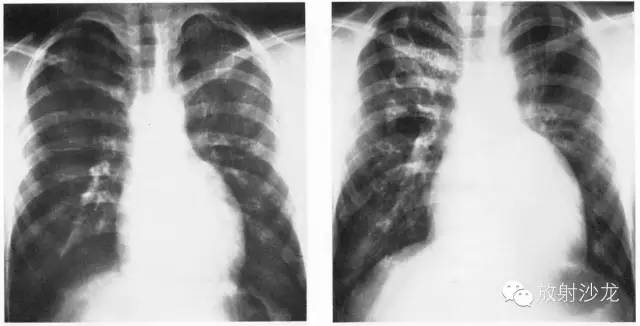

不同程度的左房增大

1、后前位:心尖左、下移位(胃泡内、越出锁骨中线)相反搏动点上移,左心缘延长、圆隆并向左下扩大。

2、左前斜位:心后缘向后下延伸与脊柱重叠,室间沟前下移。

3、侧位:食道前间隙消失,心后间隙变窄。